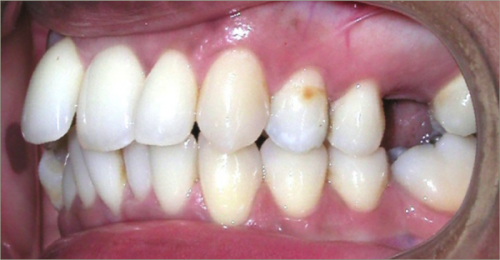

32 year old female:

Diagnosis:

- Previously lost upper first molars

- Severe lower arch crowding

- Midline discrepancy

- Narrow upper arch form

Treatment:

- Extraction of lower right first bicuspid

- Substitution of upper second molars for first molars

- Full fixed appliances

- 23 months